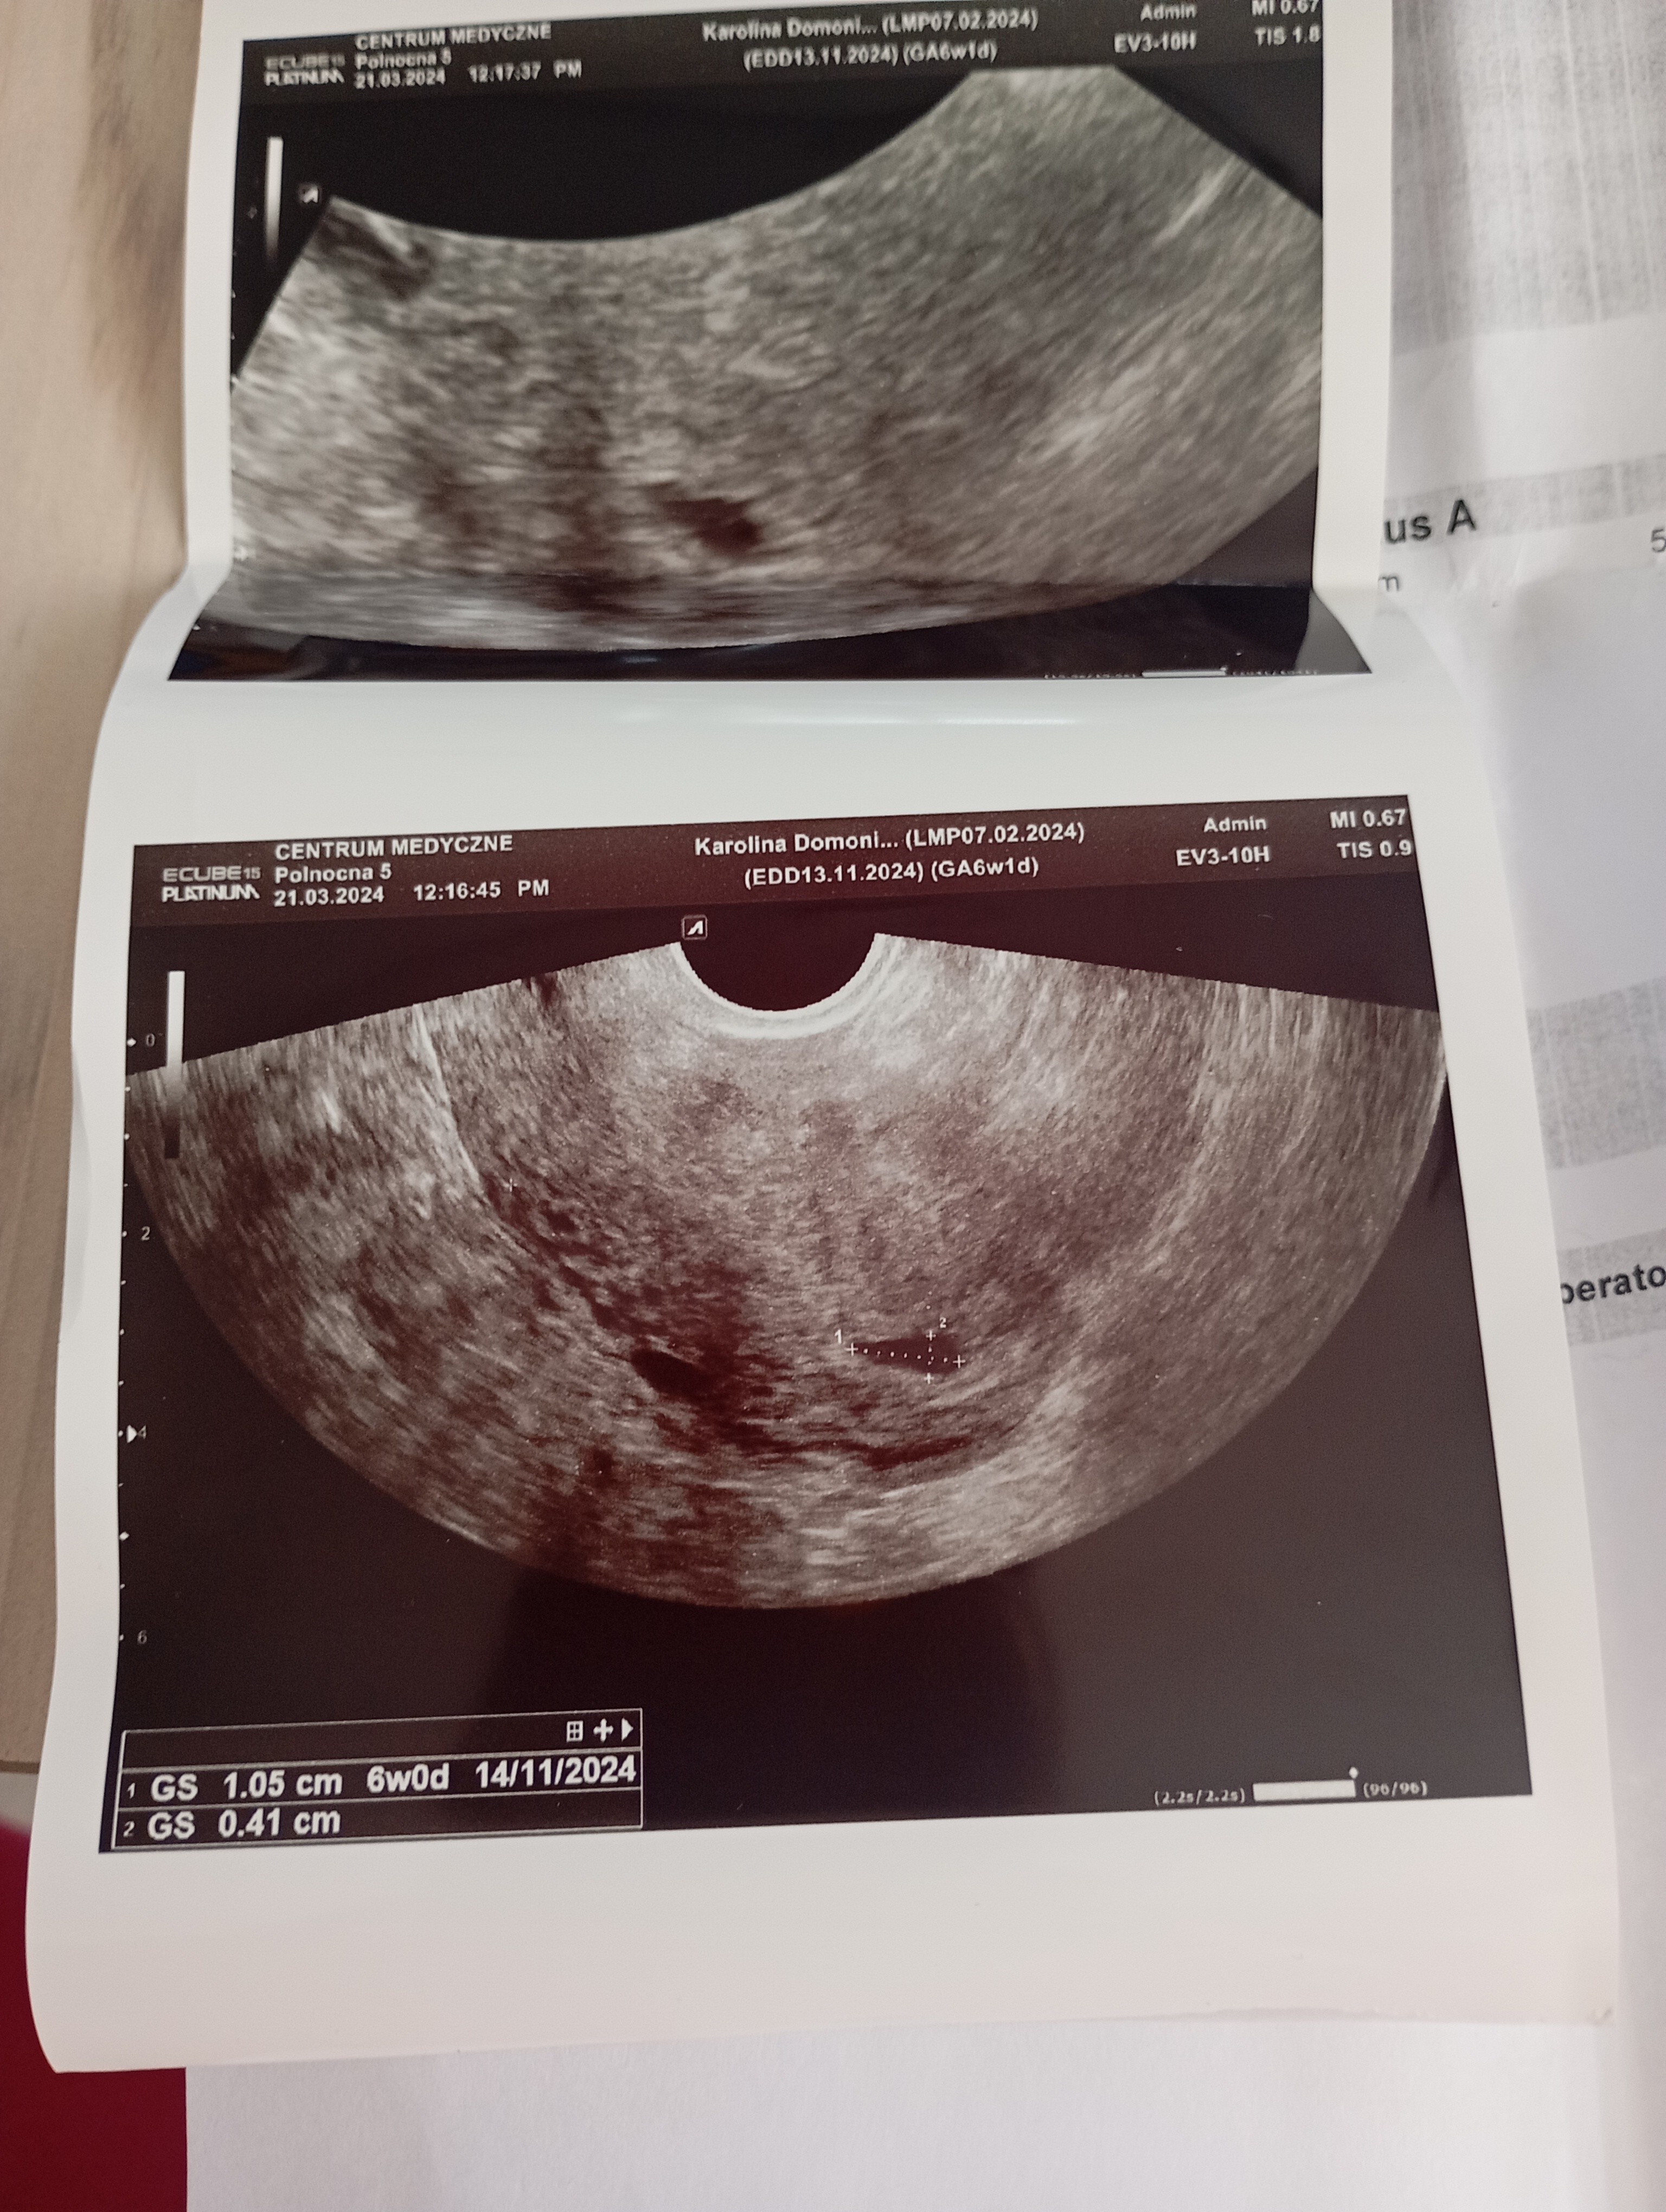

Część dziewczyny. Właśnie wróciłam od lekarza . Na USG nie widać zarodka. Strasznie nie miła lekarz nie chciała nic mówić. Kazała przyjść za tydzień i zleciła luteinę. Beta ładnie rośnie. Czy ktoś się na tym zna ?

• IMG_20240321_142521.jpg

IMG_20240321_142521.jpg

1,8 MB · Wyświetleń: 554

• IMG_20240321_142523.jpg

IMG_20240321_142523.jpg

1,8 MB · Wyświetleń: 219

• IMG_20240321_142525.jpg

IMG_20240321_142525.jpg

1,9 MB · Wyświetleń: 225